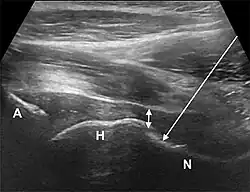

- The anterior longitudinal approach: the probe is aligned along the long axis of the femoral neck. The needle is introduced from an anteroinferior approach and is passed into the anterior joint recess at the femoral head-neck junction.

- The anterolateral approach, with the ultrasound probe oriented axially and the femoral head and acetabular rim in view. This often shortens the distance from needle skin entry to joint compared to the longitudinal approach making it a useful approach in larger patients. The introduced needle remains lateral to the femoral neurovascular bundle, and the needle is advanced until its tip rests on the femoral head.

- A low-frequency curvilinear probe (5-2 MHz), coated with a glue sterile dressing table, is put in a transverse plane parallel to the inguinal ligament and utilized to recognize the femoral artery and vein over the hyperechoic femoral head. The probe is then transferred laterally to just over the hyper-echoic femoral head and rotated into an oblique sagittal place so the probe mark is targeted towards the umbilicus.